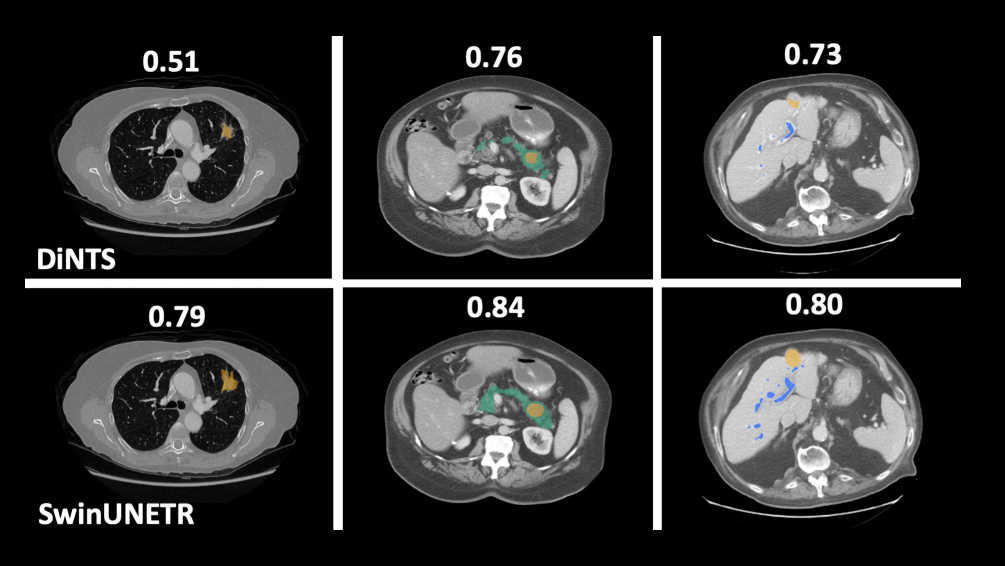

Сегментирование злокачественных образований

Применение технологий компьютерного зрения для обнаружения патологий органов человека

• Анализ МРТ, КТ, рентгеновских снимков для выявления злокачественных образований